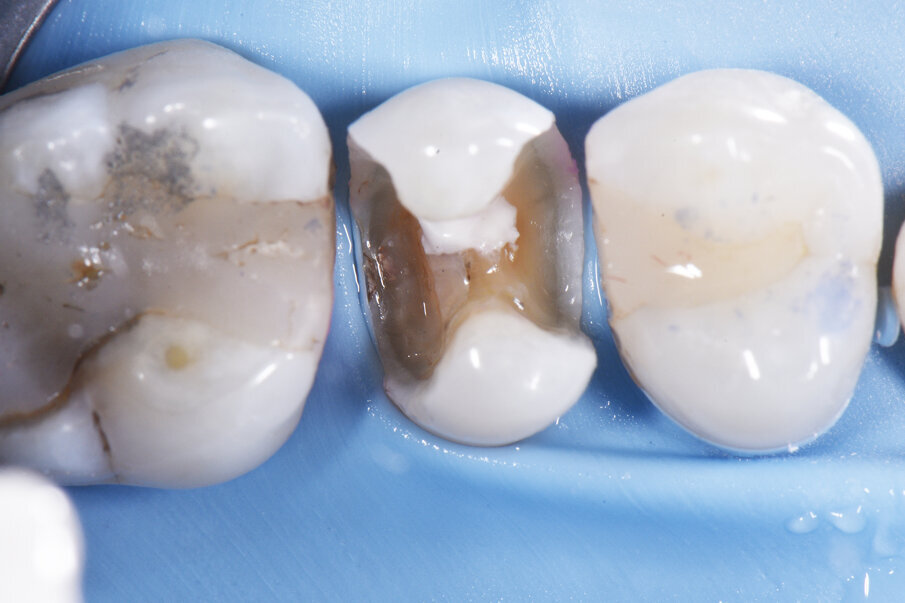

Palodent® V3 sectional matrix set-up showing a re-creation of an ideal line angle anatomy all in one solution.

Zoomed out view showing diametrically-opposing Palodent® V3 rings with Palodent® V3 matrices overlapping each other in a one-step solution driving the rebuilding of proximal and axial contours predictably.

The Palodent® V3 matrix permitted efficient reconstruction and placement of initial layers in the extended proximal box situation, obviating the need to free-hand sculpt line angles prior to placement of the sectional matrix assembly.